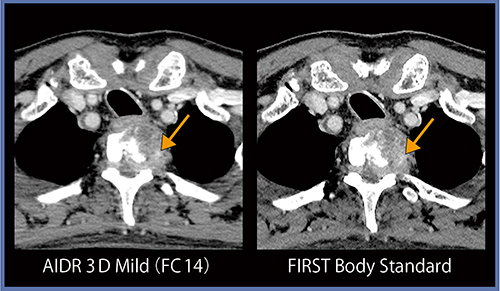

●症例6:大腿骨骨折

図7では,AIDR 3DとFIRSTの両方で骨折が認められ,その部分の骨髄の濃度が上昇しており出血が示唆される。やや近位側の画像(図8)を見ると,背側部の濃度上昇はAIDR 3Dでも確認できるが,腹側部についてははっきりしない。しかし,FIRSTでは骨髄の淡い濃度上昇が同定しやすくなっている(→)。これは,空間分解能の向上に伴いパーシャルボリューム効果が低減したためと考えられる。

骨髄の濃度上昇は,はっきりしたものであればAIDR 3DとFIRSTの描出能に差は見られないが,淡い濃度上昇ではFIRSTがより有用な可能性がある。

図7 症例6:大腿骨骨折

図8 症例6と同一症例(やや近位側)